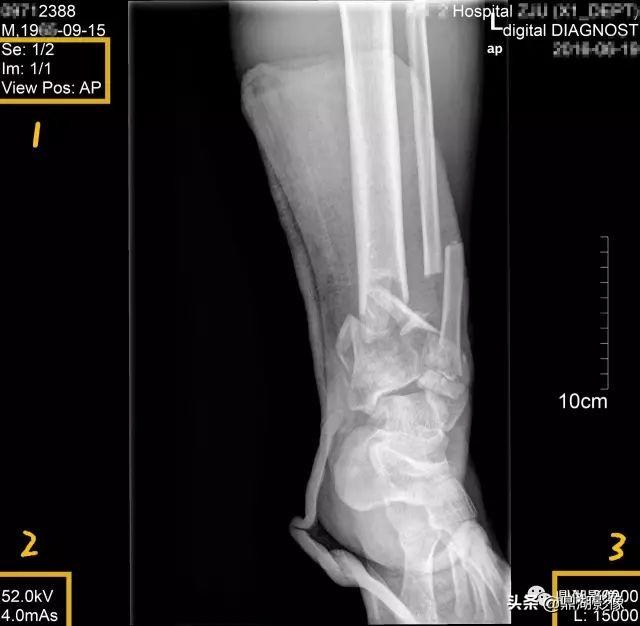

1区:SE为序列,1/2意为图中检查总共正侧位两张检查,此为第一张,View Pos为投照位信息,A、P、R、L为方位,分别为前后右左;所以图中AP为前后位。

2区:是扫描参数,上面的52KV是电压,临床中技术老师会根据病人的具体情况调节电压大小;下面的mAs是电流乘时间,根据时间可知道做检查所受的剂量。

3区:为显示视野